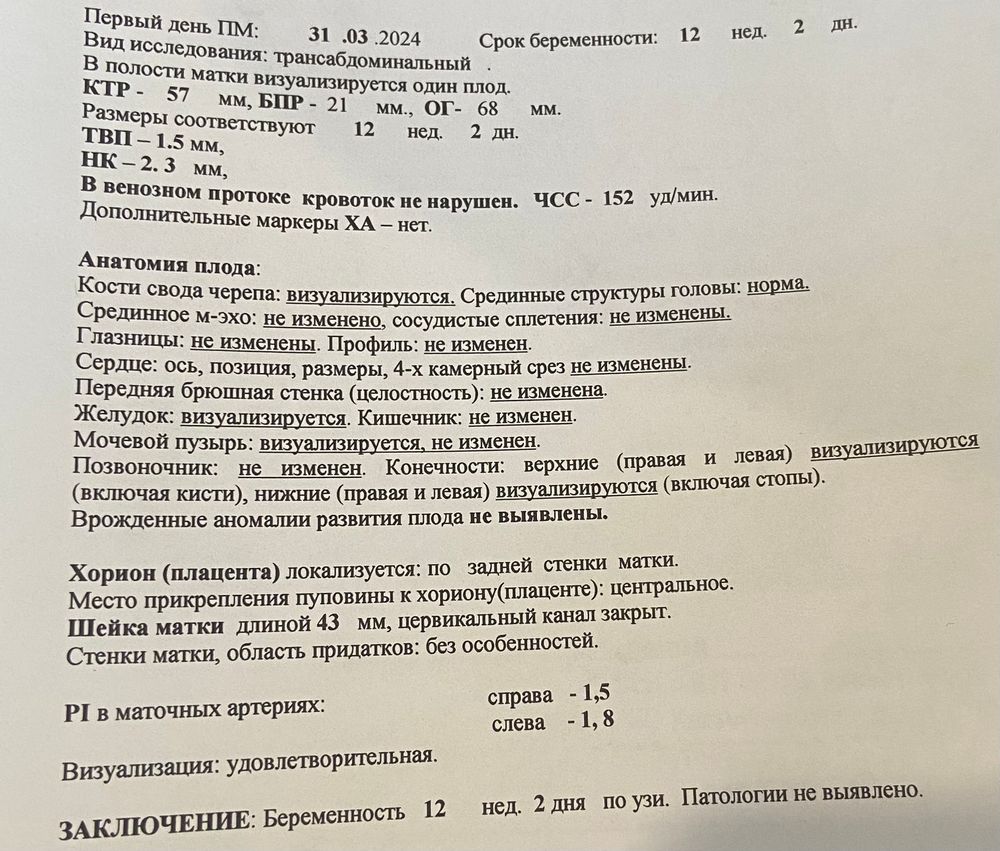

я вот все думаю, низкий ли риск трисомия 21- 1:1100?

Вообще в совокупности по всему скринингу- все хорошо ведь? Хочется успокоится до приема врача ( а прием 11 июля только😁)

я вот все думаю, низкий ли риск трисомия 21- 1:1100?

Вообще в совокупности по всему скринингу- все хорошо ведь? Хочется успокоится до приема врача ( а прием 11 июля только😁)

Трисомия 21 1:1100 низкий риск. Вопросы по преэклампсии и задержке развития (кровотоки нужно смотреть)